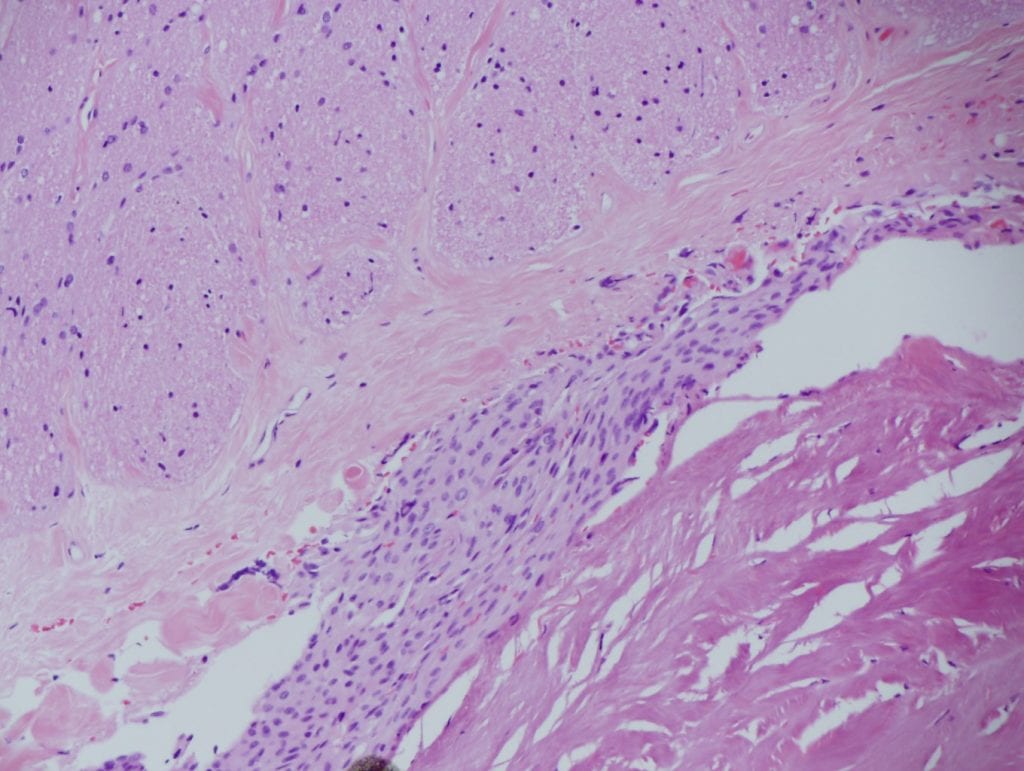

Case Report Spontaneous pineal apoplexy in a pineal parenchymal tumor of intermediate differentiation Authored by: Ching-Chun Wang (Nepean Hospital) Jennifer Turner (St. Vincent’s Hospital) Timothy Steel MBBS, FRACS (St Vincent’s Hospital) Abstract Pineal apoplexy is a rare clinical…Dr Timothy SteelMarch 10, 2013